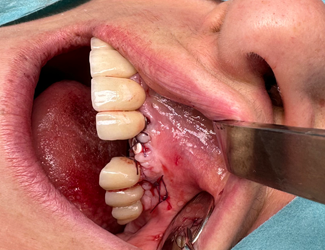

Yngre kvinna som genom trauma förlorat tänderna 11-22. En både horisontell samt vertikal defekt i ett estetiskt utmanande område. Ett Yxoss 3d printat membran framställs genom planeringsverktyget, i detta fall IO scan samt CBCT som underlag. En pre-protetisk uppvaxning på tänkt suprakonstruktion framställs för att förutsäga kommande protetik samt tänkt benvolym. Partikulerat ben appliceras i membranet som sedan fixeras på plats. Efter 6 månaders läkning avlägsnas membranet. Regenererat ben med obefintligt pseudoperiost påvisas, implantat kan placeras med god marginal samt goda protetiska förutsättningar.

Bendefekt kliniskt

Fixerat Yxoss membran